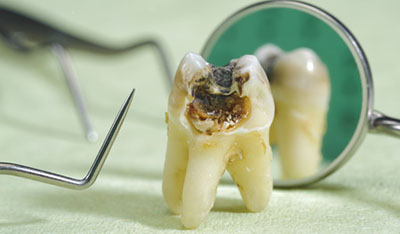

При появлении каверны усиливается чувствительность к изменению температурного режима, иногда — механического воздействия. Такие каверны, в просторечие называемые «дырками» в эмали, и становятся предметом беспокойства пациентов с больными зубами. В них начинает скапливаться еда, может появиться характерный неприятный запах.

При переходе кариеса в глубокую форму возникают кратковременные, резкие боли от разных видов воздействий. При устранении раздражителя они тоже стихают.

При появлении каверны проводится её санация различными способами удаления отмерших тканей. Затем производится пломбирование и выравнивание поверхности со шлифовкой.

Глубокие поражения, осложнённые пульпитом, требуют длительного лечения. В некоторых случаях врачу приходится удалять нерв и очищать корневой канал с последующим его пломбированием.

Лечение кариеса зубов предполагает удаление пораженных болезнью участков зубов (дентин, эмаль). Для удаления используется бормашина. После этого зуб незамедлительно пломбируют, то есть восстанавливают его анатомическую форму, применяя пломбировочные материалы.